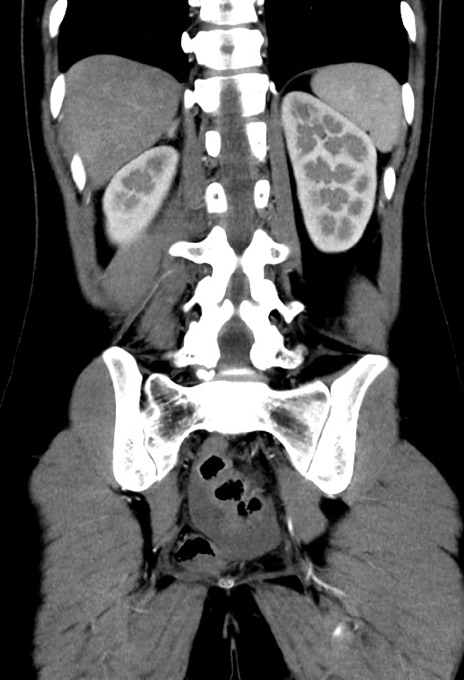

症例17(冠状断像)

【症例】20歳代女性

【主訴】嘔吐、下腹部痛

【現病歴】昨日夕食後に嘔吐し下腹部痛が出現。本日になっても嘔吐持続し改善しないため来院。

【身体所見】意識清明、BT 37.2℃、BP 108/67mmHg、腹部:平坦、やや硬、下腹部正中から右にかけて圧痛あり、反跳痛軽度あり、tapping pain(+)。

【データ】WBC 13600、CRP 14.94